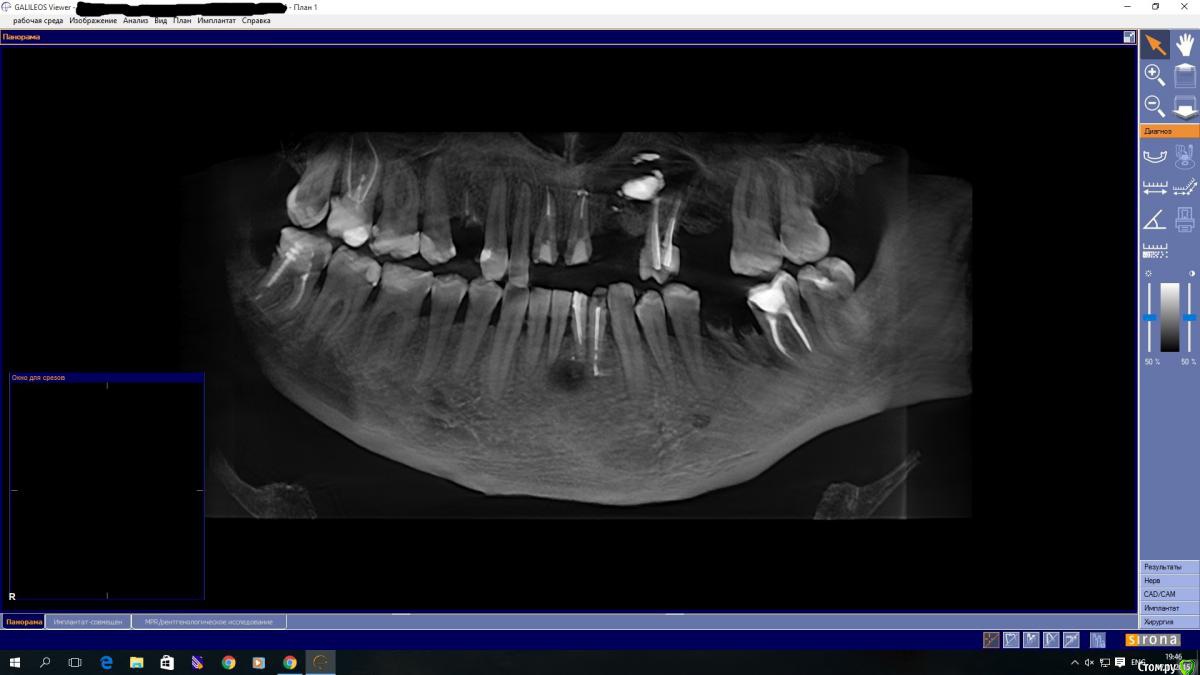

Ponchik Опубликовано 17 ноября, 2015 Поделиться Опубликовано 17 ноября, 2015 (изменено) Пациента ничего не беспокоит. В анамнезе травма 2 сегмента 7 лет назад. Пришел с целью протезирования. Ортопед удалили 22 и направил кисту убрать. Сделали прицельный.Потом захотелось КТ. КТ вышло не очень, но общее представление составить можно. Появились вопросы. На сколько велика вероятность встречи с синусом? Стоит делать амбулаторно? Опыт до этого - цистэктомии в пределах 1-2 зубов. Думаю куда направить. Изменено 17 ноября, 2015 пользователем Ponchik Ссылка на комментарий